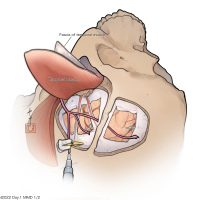

監修:谷川 緑野 / 札幌禎心会病院脳卒中センター

監修:太田 仲郎

監修:永田 雄一